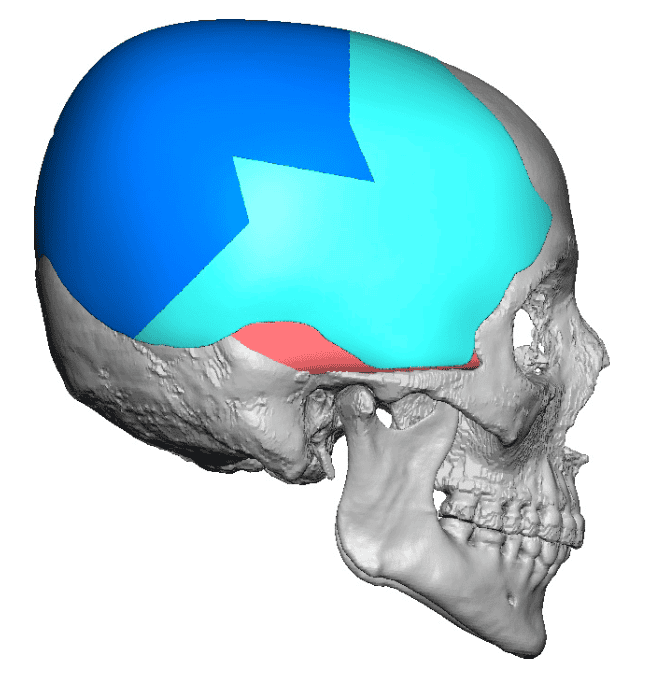

Severe narrowing skull deformity from prior sagittal craniosynostosis repair as an adult.

Complete replacement of entire skull by a custom implant with temporal fat injections.

Severe narrowing skull deformity from prior sagittal craniosynostosis repair as an adult.

Complete replacement of entire skull by a custom implant with temporal fat injections.